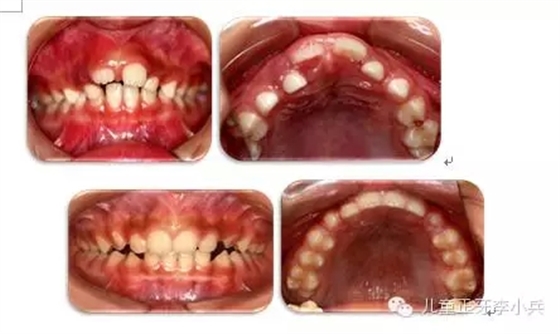

3. 牙槽骨早期塑形矯治:良好的咬合必須是上下頜骨大小位置正常、上下牙大小排列正常,以及上下牙弓的大小與形態(tài)協(xié)調(diào)。臨床功能矯形可調(diào)整上下頜骨大小與位置的不調(diào);臨床正畸治療可矯治牙齒排列異常。而上下牙槽骨的大小形態(tài)不協(xié)調(diào)的早期矯治就是牙槽骨的早期塑形。牙槽骨的發(fā)育包含牙槽骨長(zhǎng)、寬、高三項(xiàng)的發(fā)育,常見(jiàn)的牙槽骨發(fā)育異常是寬度的不足,形成功能性下頜后縮及牙列擁擠。早期的牙槽骨括弓能打開(kāi)腭中縫,擴(kuò)大牙弓寬度,增加牙弓周徑,避免功能性II類及擁擠的發(fā)生。(圖4,早期牙槽骨塑形矯治)

圖4 上頜牙弓狹窄,牙槽骨擴(kuò)弓塑形促進(jìn)上下牙弓正常發(fā)育;